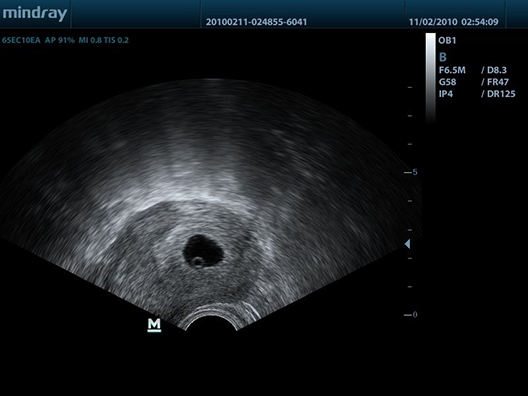

• Внутриполостной датчик Mindray 65EC10EA

Mindray DP-50 - портативный УЗИ аппарат, который является ярким представителем семейства Mindray. Он представляет собой ультракомпактное переносное устройство для проведения УЗИ-сканирования пациентов на дому или в машине скорой помощи. Аппарат оснащен черно-белым экраном и считается одним из лучших в своем классе. Он отличается высокой проникающей способностью УЗ-луча, которая обычно характерна для стационарных аппаратов.

Благодаря оптимальному 15-дюймовому экрану, впечатляющей технической оснащенности и портативной компактности, Mindray DP-50 нашел свою целевую аудиторию практически во всех сегментах современной медицины. Двухуровневая панель управления с трекболом и складывающимся экраном позволяют удобно и безопасно транспортировать систему, подобно ноутбуку. Возможности клинических исследований дополняются датчиками, которые можно приобрести дополнительно: линейные, конвексные, микроконвексные, внутриполостные, биплановые. Все зависит от ваших задач.